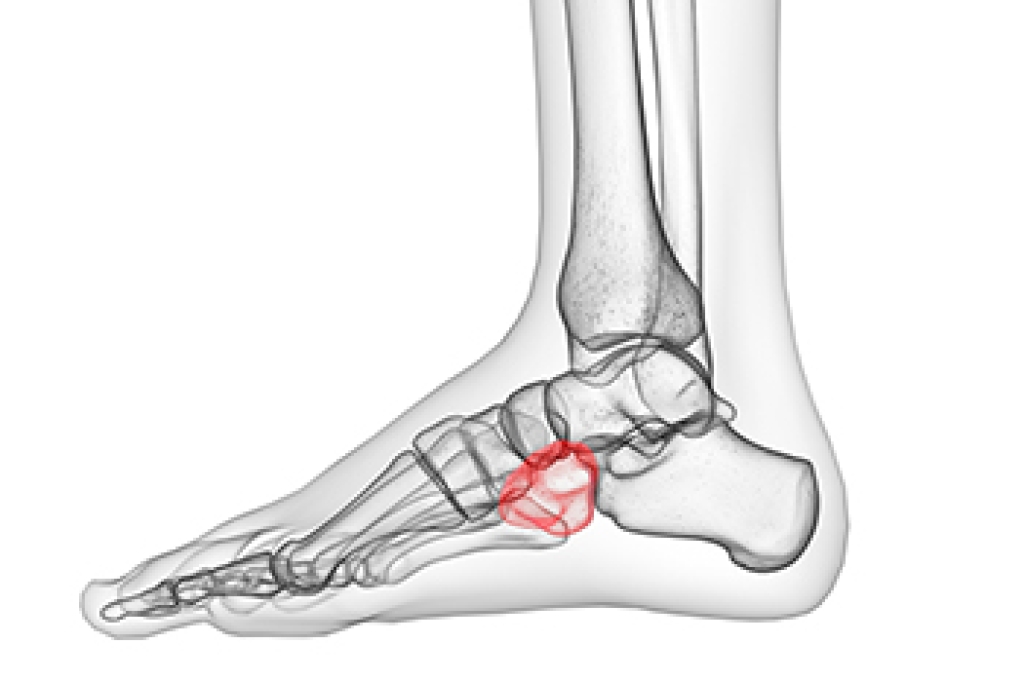

A heel spur is a bony growth that forms on the underside of the heel bone, often associated with chronic plantar fascia stress. Many patients experience sharp pain while standing or walking, especially first thing in the morning, although some may remain asymptomatic. Diagnosis typically involves a thorough physical examination and imaging tests such as X-rays to confirm the presence of the spur. Risk factors include prolonged standing, obesity, high-impact activities, flat feet, and tight calf muscles, all of which increase pressure on the heel. A podiatrist can provide effective treatment options, including custom orthotics, anti-inflammatory therapies, and minimally invasive procedures to relieve pain and improve mobility. If you have heel pain, it is suggested that you promptly consult a podiatrist who can accurately diagnose and treat heel spurs.

Heel spurs are formed by calcium deposits on the back of the foot where the heel is. This can also be caused by small fragments of bone breaking off one section of the foot, attaching onto the back of the foot. Heel spurs can also be bone growth on the back of the foot and may grow in the direction of the arch of the foot.